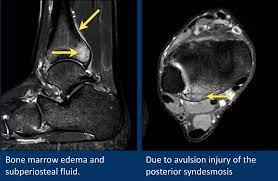

Traumatic And Non Traumatic Bone Marrow Edema In Ankle Mri A Pictorial Essay Insights Into Imaging Full Text

Traumatic And Non Traumatic Bone Marrow Edema In Ankle Mri A Pictorial Essay Insights Into Imaging Full Text from media.springernature.com